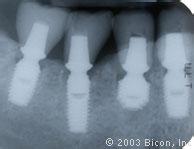

2、两段式种植体

即种植体基台与固位体分为两段而不是一个整体的一类种植体。手术时,与骨组织结合的固位体和与牙龈组织结合的基台是前后分别进行两次手术植入完成的,而在基台与固位体两段之间是通过种植体中心螺丝将其相连成为一个整体。手术先将固位体植入骨组织内,缝合伤口,经4-6月待种植体固位体在完全无负载的休息状态下与骨组织产生骨结合后,再行手术,即切开牙龈组织,通过种植体中心螺丝连接基台,拆线后即可取模并完成修复体。

两段式种植体的优点是,种植体骨结合好,不易感染,义齿的修复方式多样,其上部结构可多种选择,远期效果好,成功率高。缺点是需经两次手术才能完成。